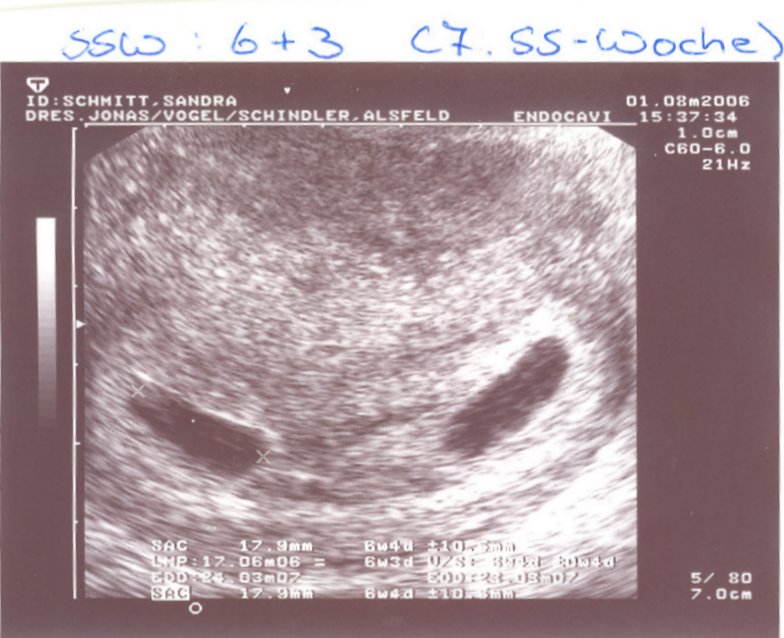

3.ICSI: Transfer am 28.07.==> POSITIV!

ES SIND ZWILLINGE!!!!!

Geburt von Lucca und Lennis am 4.2.07 in SSW 29+2